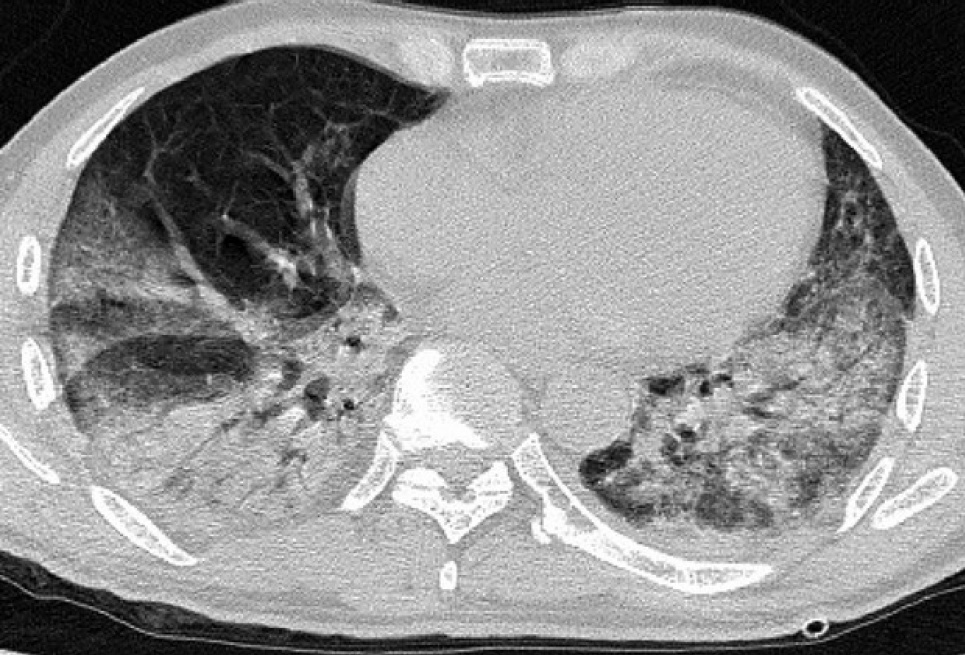

Коронавірусна інфекція COVID-19 у важких випадках захворювання призводить до атипової пневмонії. Це наочно продемонстрували медики, які показали КТ-знімки легень у пацієнтів з Китаю: на фото, що розміщені в публікації Радіологічної спільноти Північної Америки, простежується розвиток патології.

Зокрема медики звернули увагу на те, що рідина, яка накопичується в легенях в результаті шкідливого впливу вірусу на організм людини, поступово займає все більшу частину органу.

Також зазначається, що найбільш характерними ознаками пневмонії від COVID-19 були: периферійний розподіл ураження, симптом "матового скла" (туманне, матове зниження прозорості легеневої тканини з диференційованим малюнком судин і бронхів на цьому тлі), потовщення стінок судин.